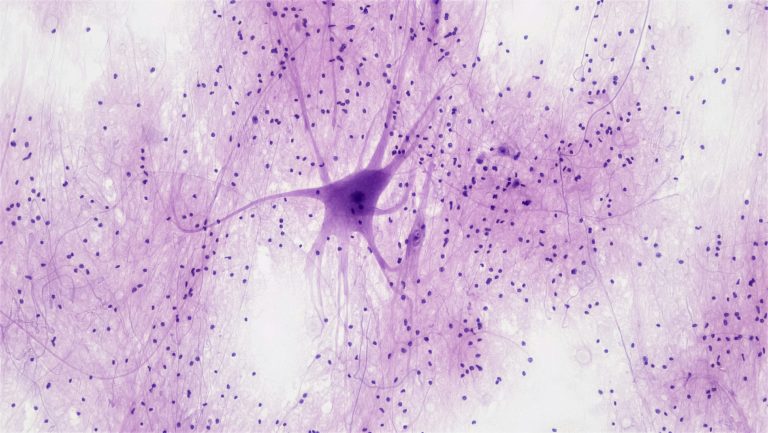

Unser erstes Knowledge-Nugget ist fächerübergreifend relevant! Die Blut-Hirn-Schranke (BHS) ist eine spezialisierte physiologische Barriere, die das zentrale Nervensystem (ZNS) vor schädlichen Substanzen schützt und den Stoffaustausch zwischen Blut und Gehirn